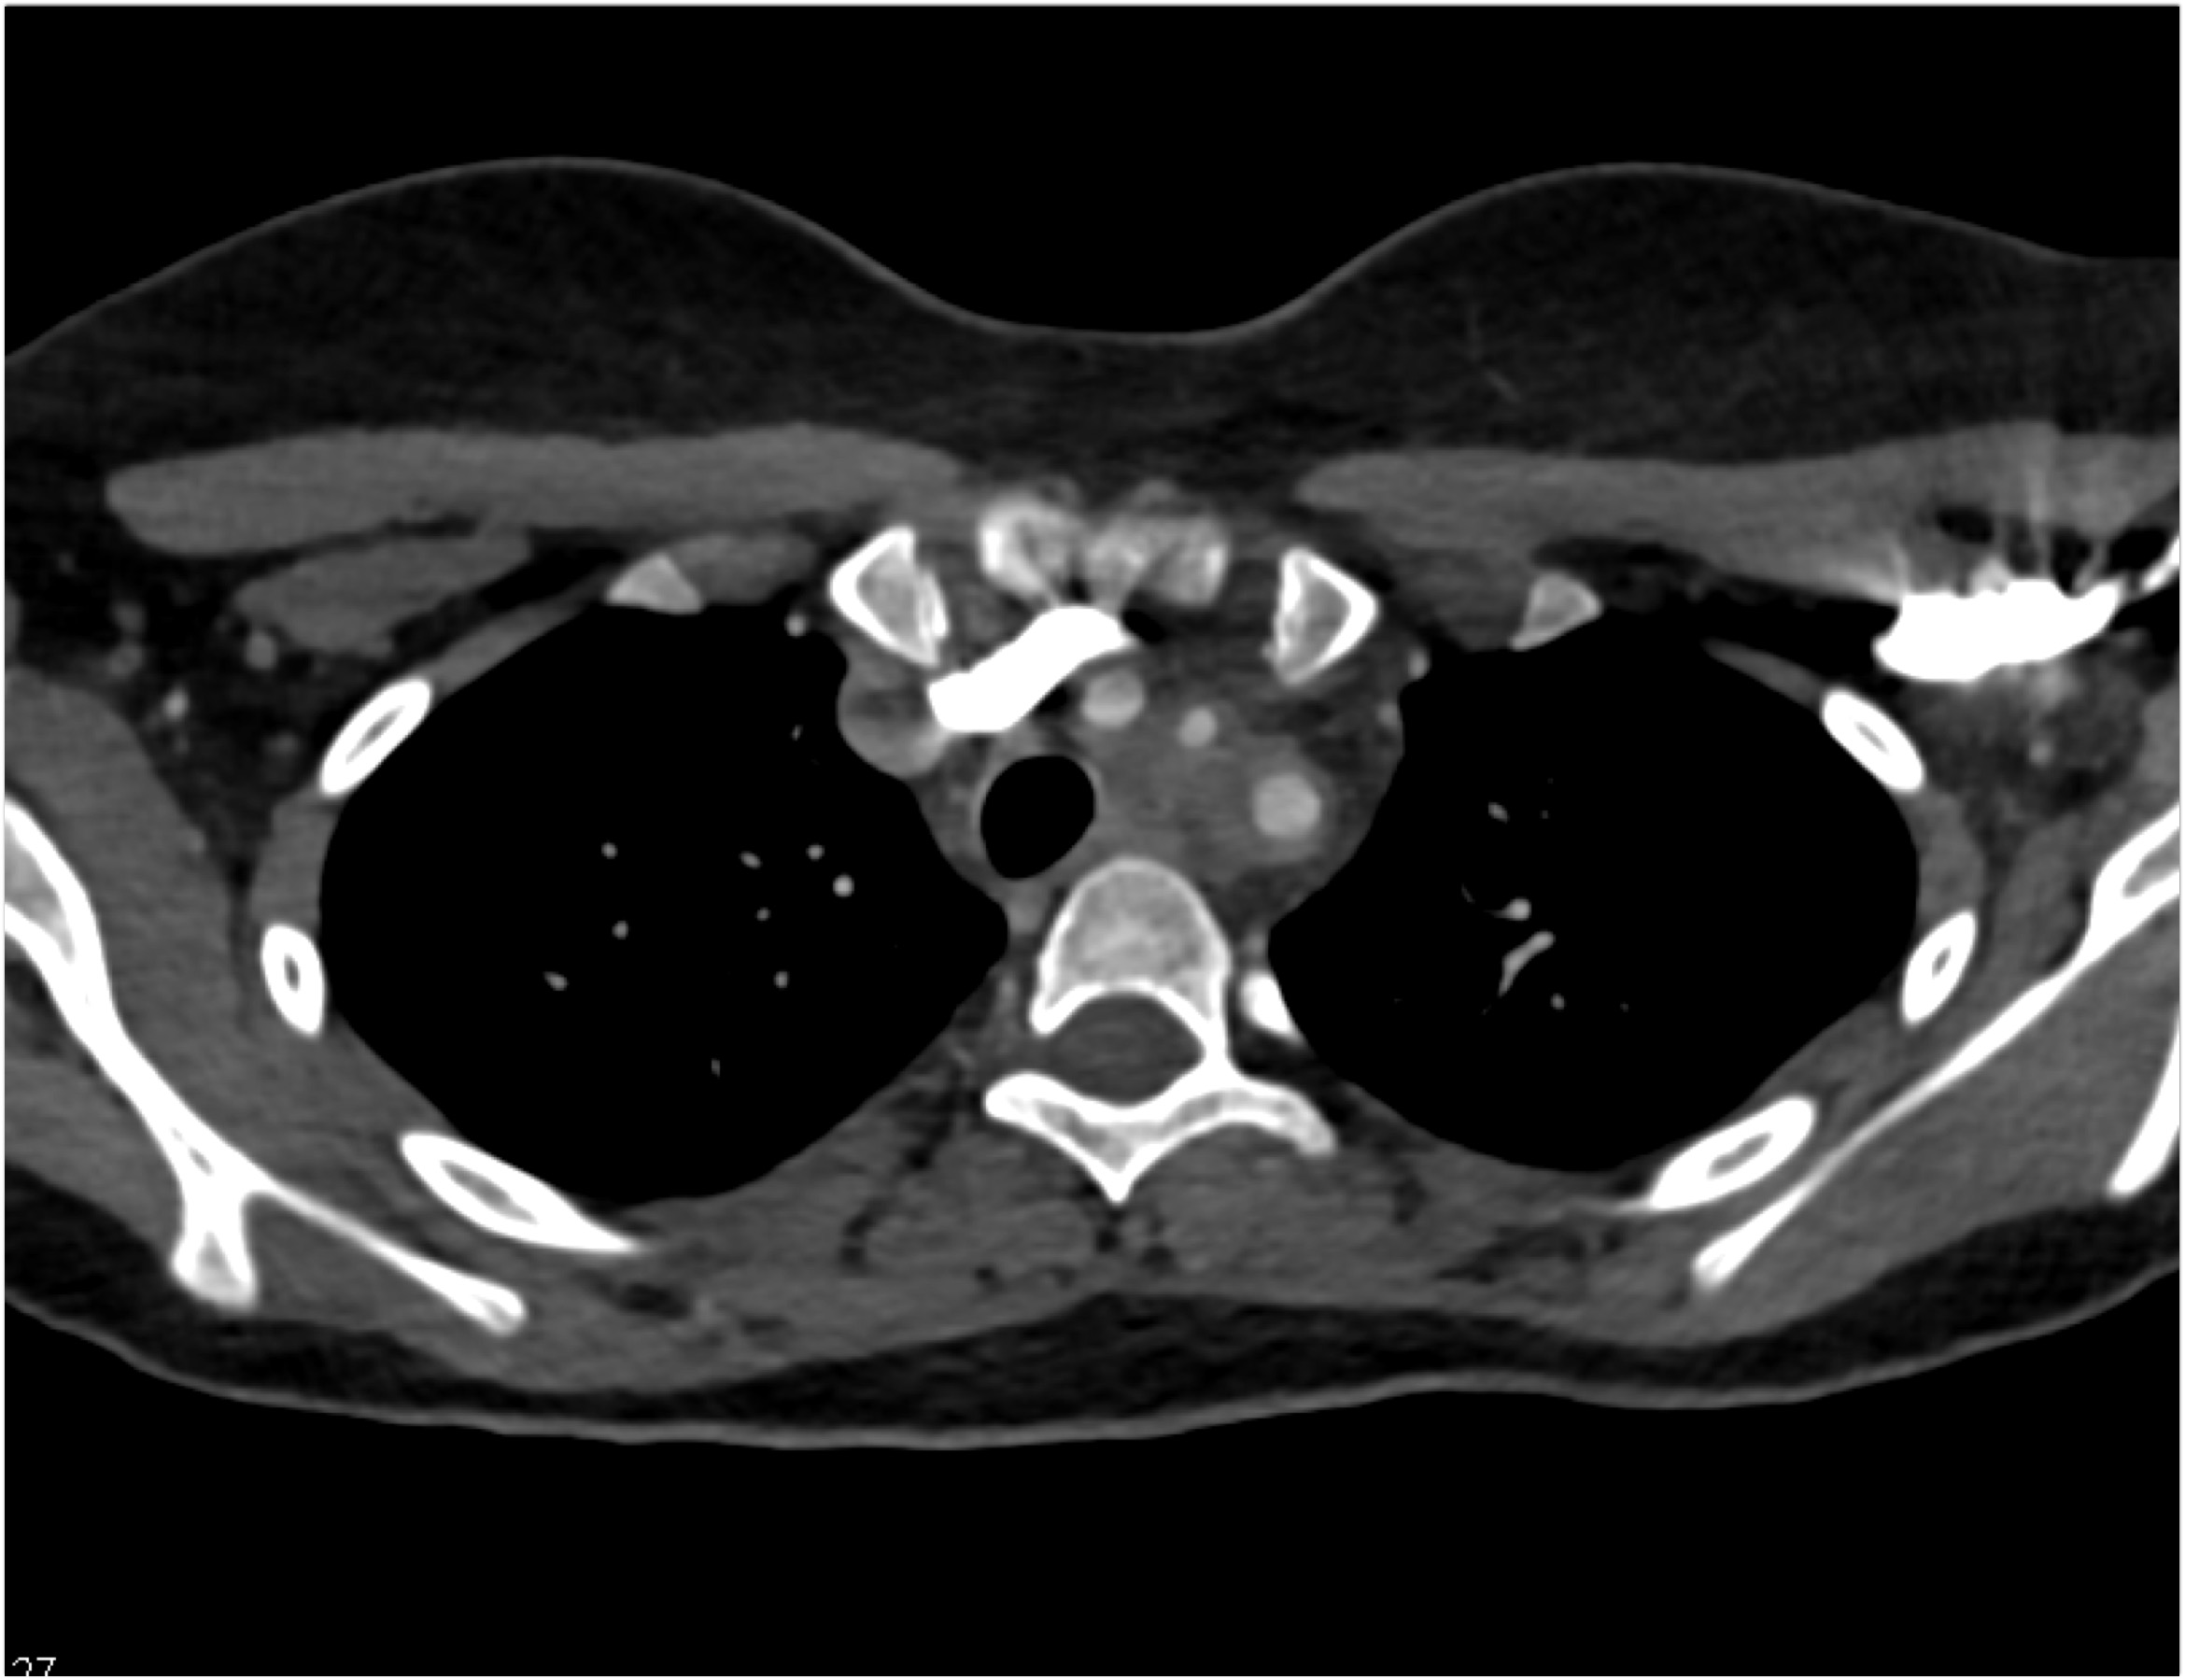

2) In this patient on dialysis for ESRD the best diagnosis is?

normal bypass graft

AV fistulae with aneurysms

vasculitis

infectious vascular disease